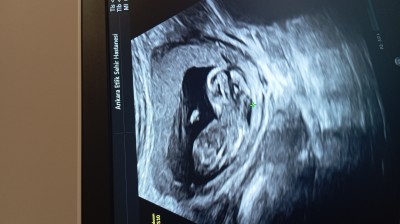

Kizlar bir hafta sonra gidicem doktora sizce cinsiyeti ne bu resmi cekmisdim

Gebelik haftası 15